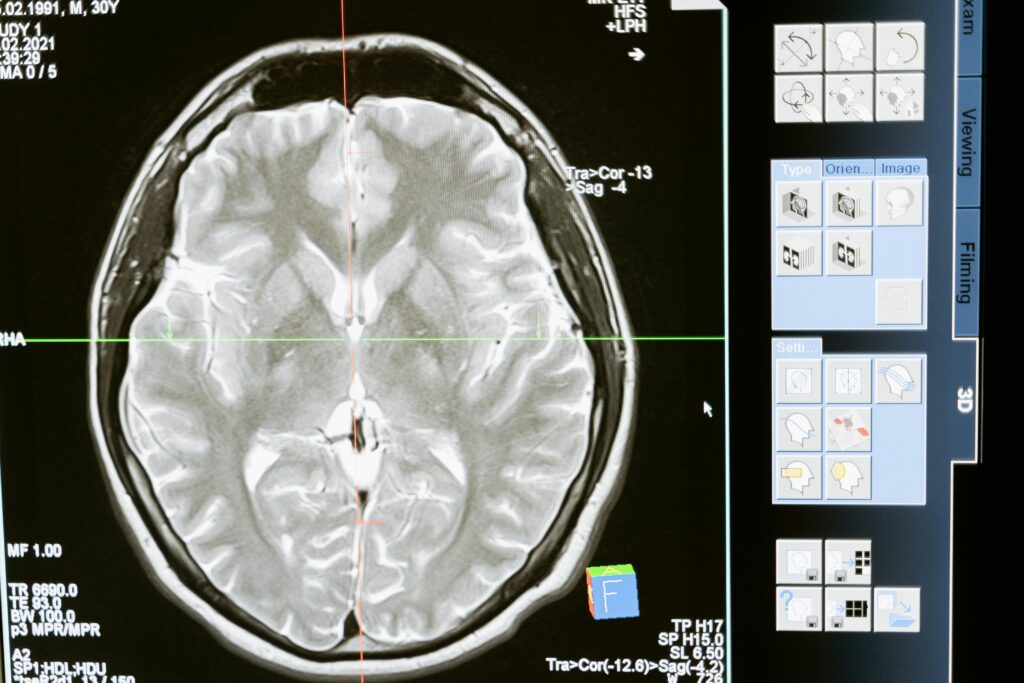

Pandora Medical Center pune la dispoziție o gamă variată de investigații neurologice avansate, menite să diagnosticheze cu acuratețe afecțiunile creierului și ale sistemului nervos. Utilizăm tehnologii de ultimă generație, precum EEG, EMG, ecografia Doppler, Holter EKG și monitorizarea tensiunii arteriale, pentru a detecta precis diverse afecțiuni. Pe lângă acestea, oferim interpretarea detaliată a analizelor de sânge, a rezonanței magnetice nucleare (RMN), a tomografiei computerizate (CT) și a testelor genetice, asigurând o evaluare completă și exactă a stării de sănătate a pacienților noștri.